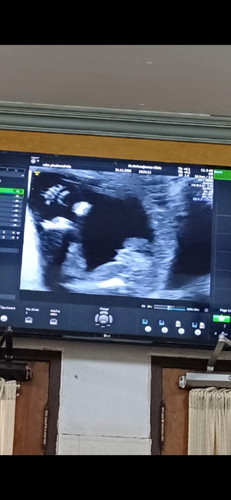

เมษายน เหมือนกันแต่ยังไม่รู้เพศเลยน้องไม่ให้เห็นเลย

ของหนูก็ทีมเมษาค่ะ19วีค1วันยังไม่ได้ถามคุณหมอเรยค่ะ

ของหนูก็ทีมเมษายนวันที่7ค่ะ20วีค4วันหมอบอกได้ลุกชาย

บ้านนี้ทีมเมษาวันที่9ตอนนี้20+4วีคแล้วผู้ชายค้า

ทีมเมษาเหมือนกันเลยวันที่13 ยังไม่รู้เพศเลยยย

ทีมเมษาค้ะ19+5วันค่ะเดือนหน้านัดซาวเพศค่ะ

ทีมชายค่ะ 18 เมษา ☺️

ทีมเมษาวันที่10คะ

บ้านนี้11เมษาค่ะ